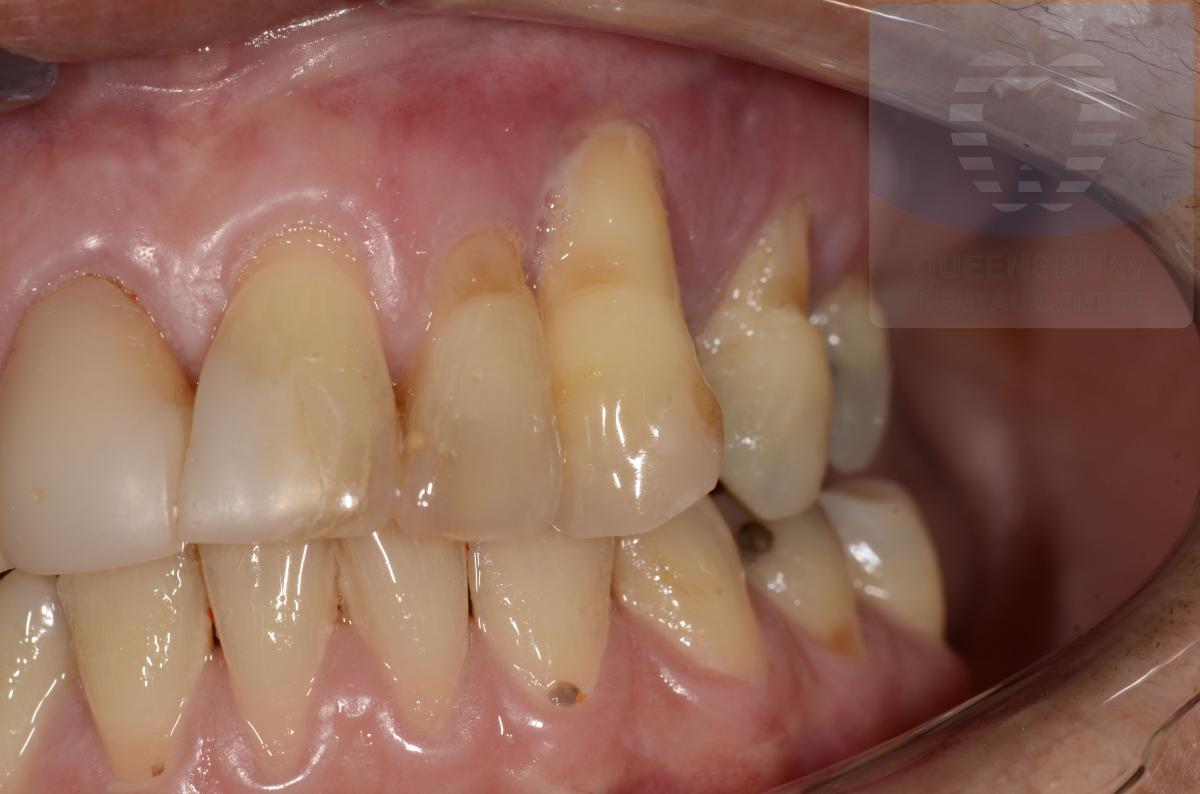

Missing teeth and loose dentures make many people avoid social settings because they are too self-conscious about their appearance. Current dental procedures, however, replace everything from a single missing tooth to a completely missing arch. Ask your dentist or dental specialist about the different dental options that are available to you. Don’t let another day go by without taking this important first step to restoring your confidence and your smile!